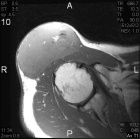

65 year old male with a one year history of an enlarging painless right shoulder mass

Zoom image: Radiological image Radiological image.